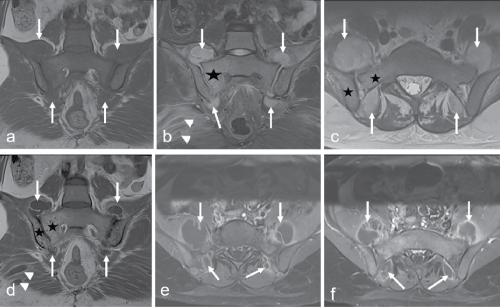

A 21-year-old female patient applied to our hospital with gluteal and lumbar pain. Physical examination revealed tenderness in the bilateral sacral-lumbar area and limitation of the bilateral hip joint. Sacroiliac joint MRI showed the bone marrow oedema, overlying soft tissue swelling, right gluteal muscles abscess and multilocular abscess involving the bilateral sacroiliac joint (Figure 1). Pyogenic sacroiliitis of sacroiliac joint is seen rarely, representing 1-2% of all cases of septic arthritis [1]. The most frequent symptom is lumbogluteal pain and the diagnosis is difficult because of the lack of symptom specifity. Staphylococcus aureus is the most detected organism in cases of pyogenic sacroiliitis [1,2]. In our case, the abscess was drained with percutaneous surgical approach and the patient responded well to antibiotic therapy.

Figure 1: Coronal T1 weighted image (a), coronal (b) and axial (c) T2 weighted images, contrast enhanced coronal T1 (d) and fat saturation axial (e,f) T1 weighted images show the bone marrow oedema in right sacroiliac joint (star), overlying soft tissue swelling, right gluteal muscles abscess (arrowheads) and multilocular abscess involving the bilateral sacroiliac joint (arrows). Contrast enhancement was seen in bone marrow eodema regions compatible with sacroilitis (star). Fluid collections competible with multilocular abscess was showed peripheral enhancement (arrows).